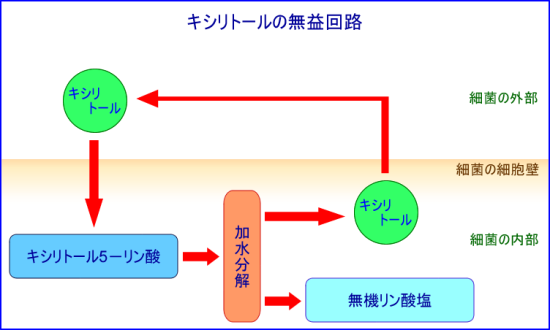

キシリトールは、このミュータンス菌に対して他の糖アルコールには見られない、特有の作用を持っています。「キシリトールの無益回路」と呼ばれるキシリトールとミュータンス菌の関係をみて見ましょう。

口腔内に運ばれてきたキシリトールは唾液に溶解して、ミュータンス菌と出会うことになります。そしてキシリトールがミュータンス菌の外部から細胞膜を通って菌体内に運ばれると、ミュータンス菌はキシリトール5-リン酸という代謝産物を産生します。これが静菌作用を持つと言われています。

さらに、キシリトール5-リン酸はミュータンス菌体内で加水分解され無機リン酸塩とキシリトールに分解します。ここで新たに分解されたキシリトールは再びミュータンス菌の外部に運び出されることになります。この過程でミュータンス菌はキシリトールをエネルギーに変換できないばかりか、逆にエネルギーを消費してしまいます。その結果ミュータンス菌は活性を失うことなり、さらに次第に数が減っていくことになります。これがキシリトール特有の虫歯予防のメカニズムです。